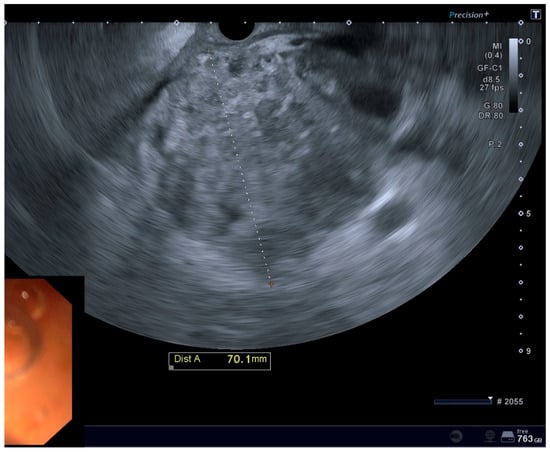

| Mean size of POFCs on EUS evaluation, width, mm | 88.8 mm |

| Mean size of POFCs on EUS evaluation, length, mm | 77.2 mm |